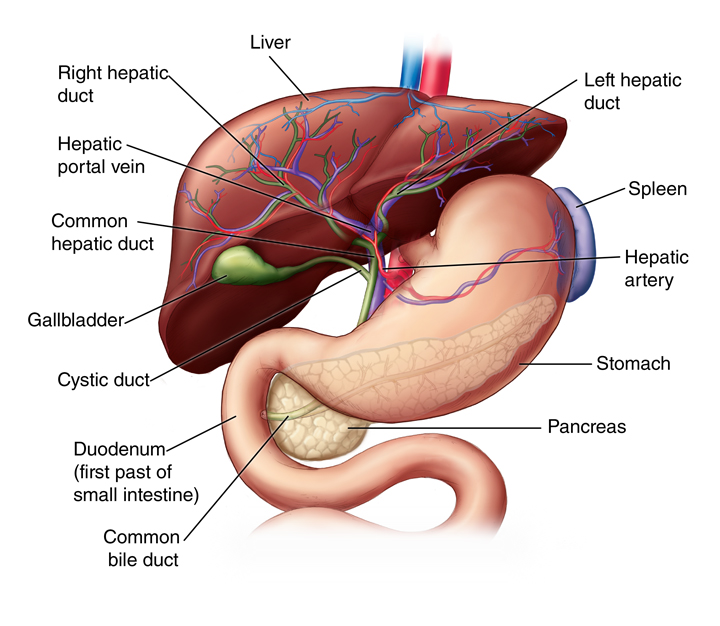

The liver is located in the upper right-hand portion of the abdominal cavity, beneath the diaphragm, and on top of the stomach, right kidney, and intestines

The gallbladder is a small organ located just below your liver in your right upper abdomen. It stores bile, which is a liquid produced in the liver. The gallbladder releases bile into the small bowel to help break down and absorb dietary fats. Normal digestion is possible without a gallbladder.

Multiple worms in CBD are well known, and ultrasound is considered a very useful modality for diagnosis and for follow-up. Also, there can be worms in bile ductules that may lead to the persistence of symptoms despite of CBD clearance. Follow-up ultrasound is thus mandatory if symptoms persist.

Pancreatic cancer begins in the tissues of your pancreas — an organ in your abdomen that lies behind the lower part of your stomach. Your pancreas releases enzymes that aid digestion and produces hormones that help manage your blood sugar.